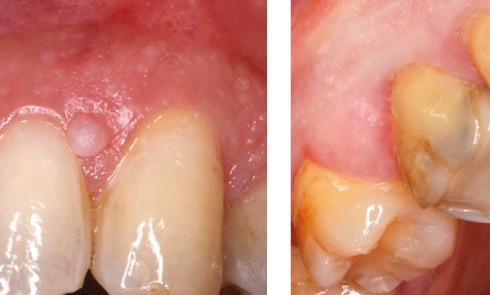

Article réservé à nos abonnés Kystes et pseudo-kystes gingivaux

Cas 1  Motif de la consultation. Patient de 50 ans venu consulter pour la découverte fortuite par son chirurgien-dentiste d’une...